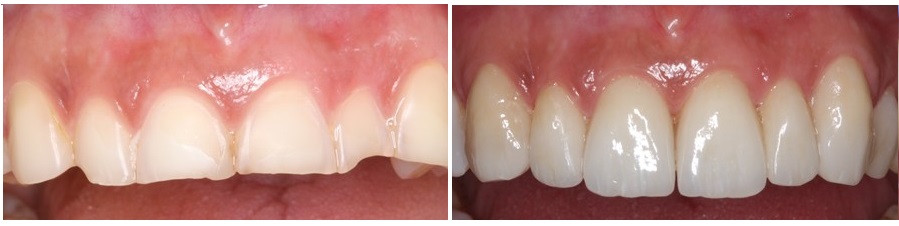

Βλέπουμε στην αριστερή φωτογραφία τις όψεις από ρητίνη που κατασκευάστηκαν για τις υπερώιες επιφάνειες των δοντιών της άνω γνάθου και δεξιά τις όψεις πορσελάνης που τοποθετήθηκαν σε επόμενο στάδιο για την εξωτερική πλευρά των ίδιων δοντιών.

Δημιουργούμε ένα είδος "σάντουιτς" από αποκαταστάσεις, που στο εσωτερικό τους περιέχουν το δόντι της ασθενούς, χωρίς να αφαιρούμε από αυτό επιπλέον οδοντική ουσία.

Η εικόνα των πρόσθιων δοντιών της άνω γνάθου μετά την τοποθέτηση αυτών των αποκαταστάσεων, φαίνεται στην ακόλουθη φωτογραφία.